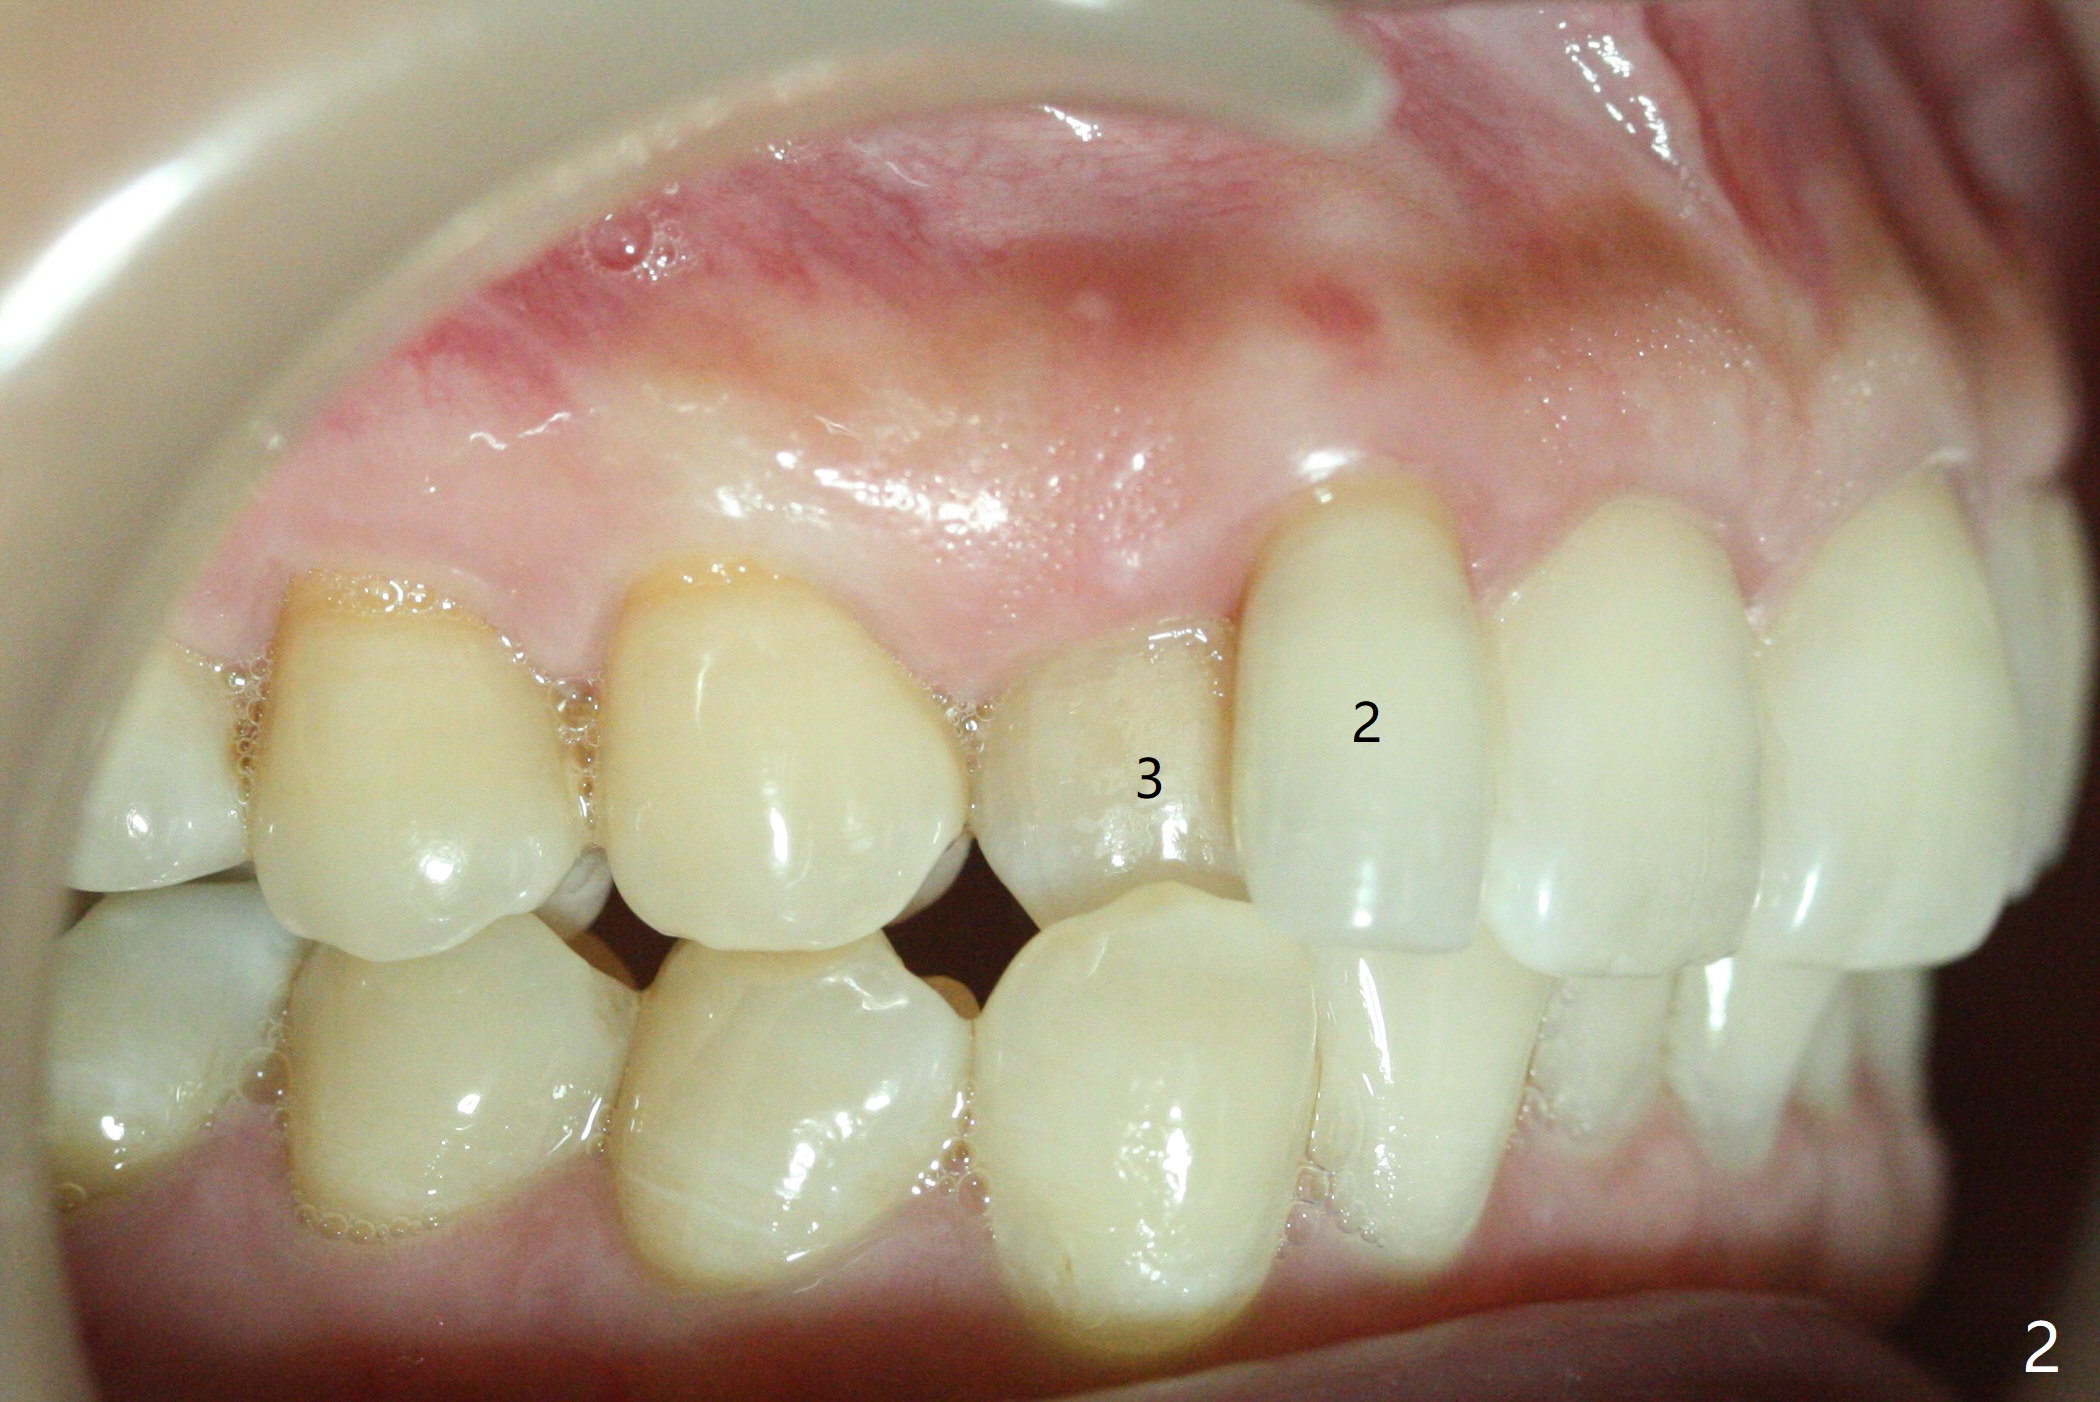

A 54-year-old woman seeks treatment for the tender upper right lateral incisor (Fig.1-4: 2 because of palatal cervical caries (Fig.3 <) and periapical radiolucency (*)), which overlaps with the palatal canine (3). One of treatment options is to extract the lateral and to orthodontically move the canine to the position of the lateral, particularly the root (Fig.5 arrow). When the lateral is removed, the labial bone of the canine is thin (Fig.6). Allograft is placed (Fig.8 * and dashed line), covered with Amnion-Chorion Allograft (Bioxclude) and sutured with 4-0 PGA (Fig.7). The wound heals 9 days postop (Fig.9,10). The patient is grateful because of no pain, which she thinks is due to bone graft, whereas Amnion-Chorion membrane is another contributory factor. The lateral root convexity remains 1 month postop (Fig.11 *); she is undecided upon orthodontic treatment.